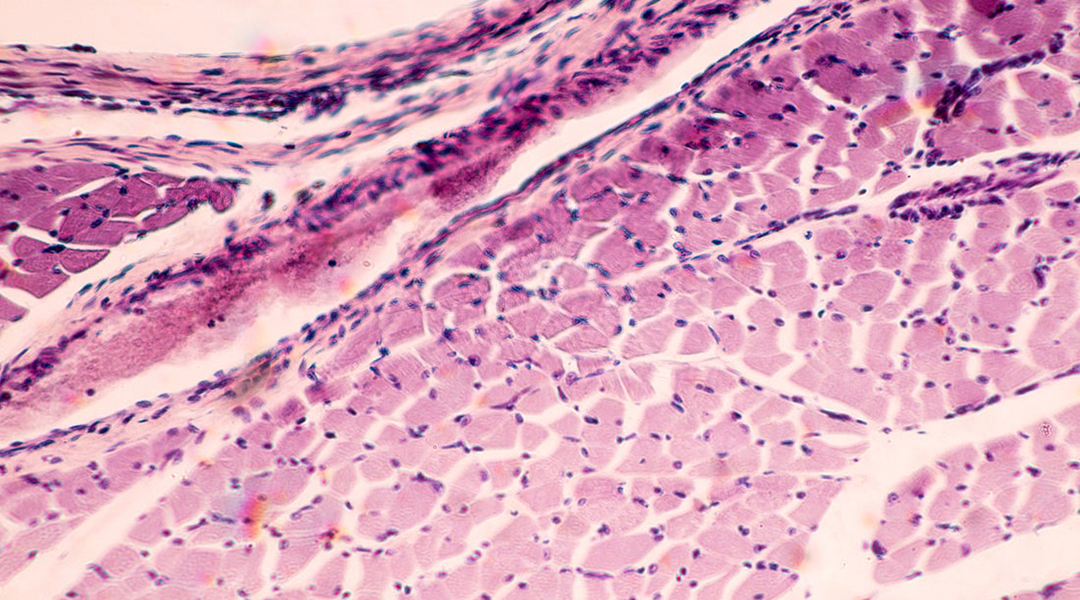

Skeletal muscle under microscope. Image credit: Shutterstock